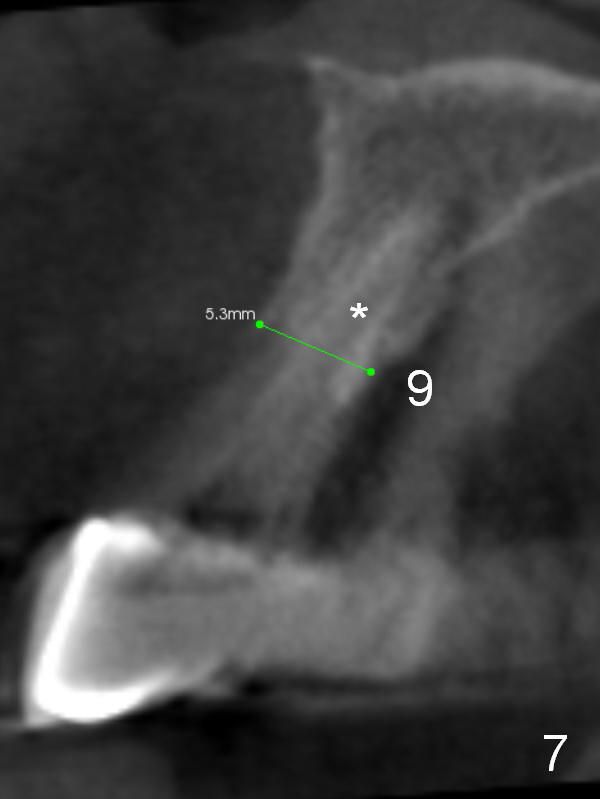

Immediate implant at #9 was aborted (Fig.7 *) because it was too closed to that at #10. Since the ridge is wide, it is worthy to try again. Place the implant as mesial as possible.